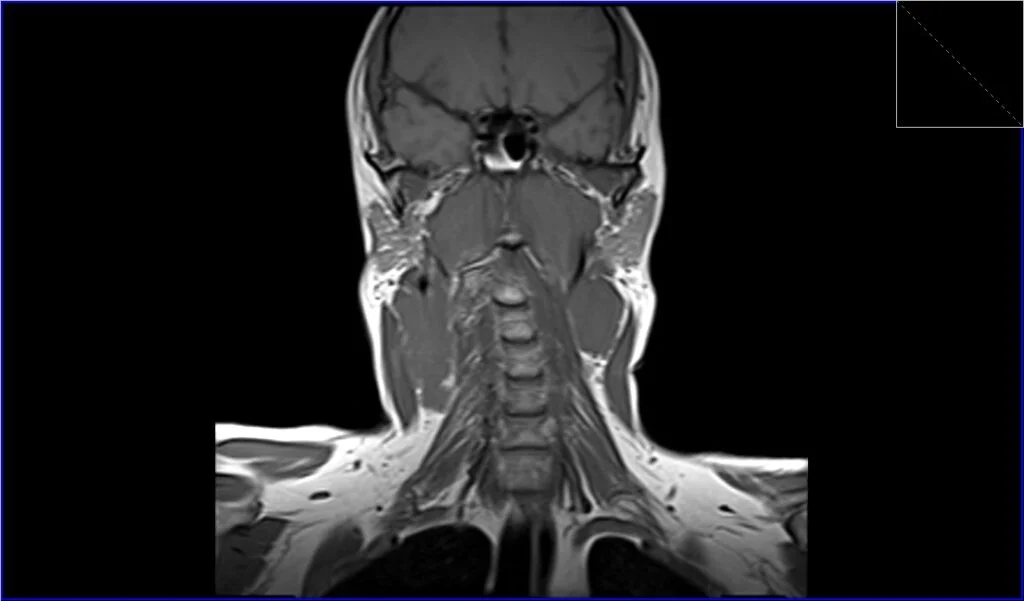

T1-Weighted Images (T1): On T1-weighted MRI sequences, lymphoma typically appears as a mass with intermediate to low signal intensity, which means it’s generally darker than the surrounding fat and lighter than the muscles.

T1 coronal image shows Lymphoma